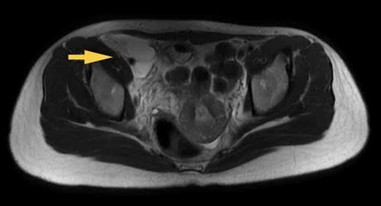

- MRI tiểu khung có tiêm chất tương phản: Vùng bẹn phải, nằm dọc bó mạch chậu ngoài và đùi chung có khối tổ chức bao gồm phần đặc ngấm thuốc sau tiêm và phần dịch, trong có vách, bờ không đều, ranh giới rõ, đè xẹp tĩnh mạch chậu ngoài, ôm quanh động mạch chậu ngoài (>180 độ) nhưng không gây hẹp lòng mạch, kích thước khối 29x66x77mm, không thấy thâm nhiễm xung quanh, lân cận có vài hạch hình bầu dục, bờ đều, lớn nhất kích thước 7x10mm

Hình 5: Khối lớn vùng bẹn phải đè xẹp tĩnh mạch chậu ngoài, ôm quanh động mạch chậu ngoài (>180 độ) nhưng không gây hẹp lòng mạch 29x66x77mm( mũi tên vàng)